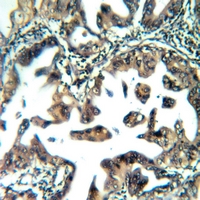

Immunohistochemical analysis of ATP5S staining in human liver cancer formalin fixed paraffin embedded tissue section. The section was pre-treated using heat mediated antigen retrieval with sodium citrate buffer (pH 6.0). The section was then incubated with the antibody at room temperature and detected using an HRP conjugated compact polymer system. DAB was used as the chromogen. The section was then counterstained with haematoxylin and mounted with DPX.